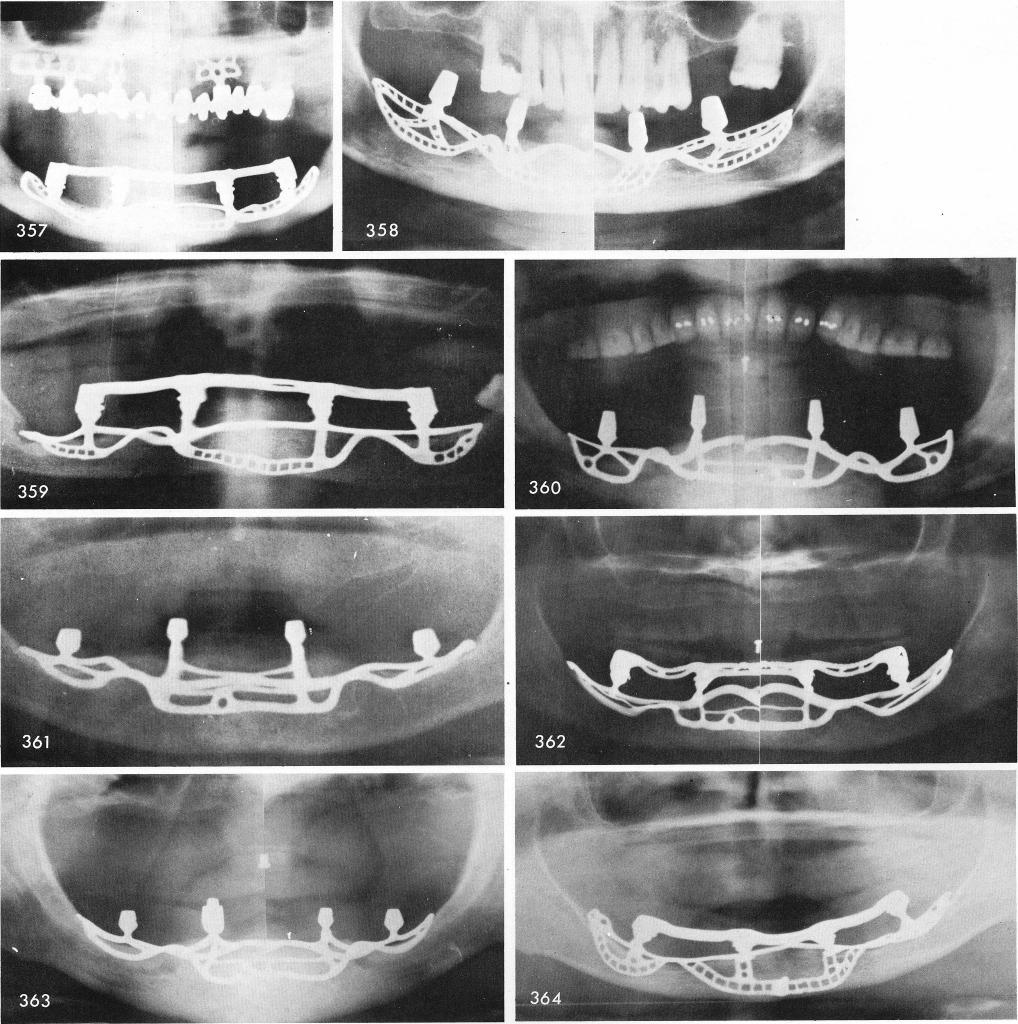

Figs. 357 through 378 shows x-rays of various subperiosteals.